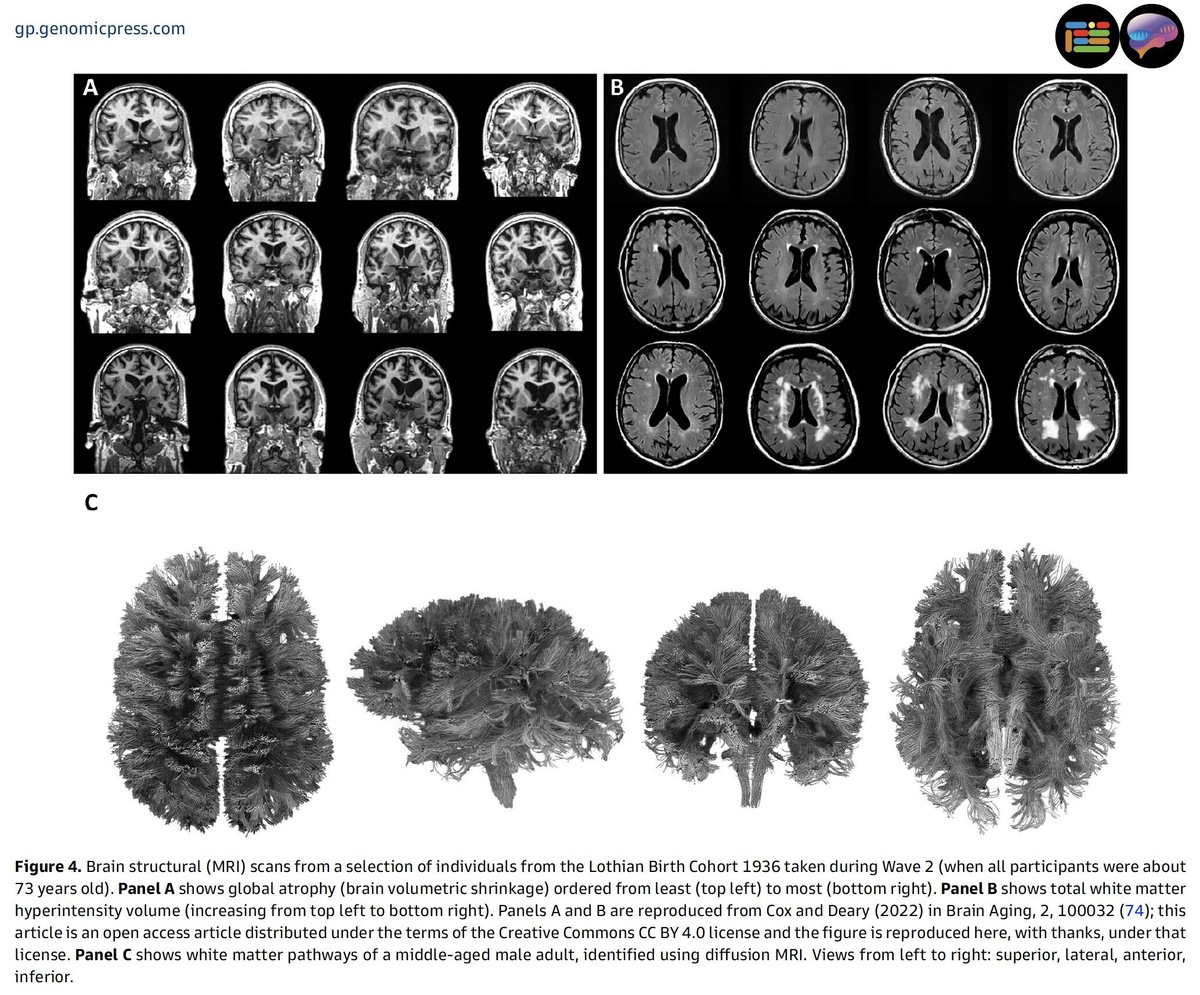

Исследование также показало, что старение мозга протекает по-разному у людей одного возраста. Особенно интересны результаты, касающиеся вариаций в здоровье мозга, выявленных с помощью передовых методов визуализации. Эти данные открывают возможности для изучения факторов, которые могут повлиять на различия в мозговом здоровье и, возможно, быть изменяемыми с помощью образа жизни.